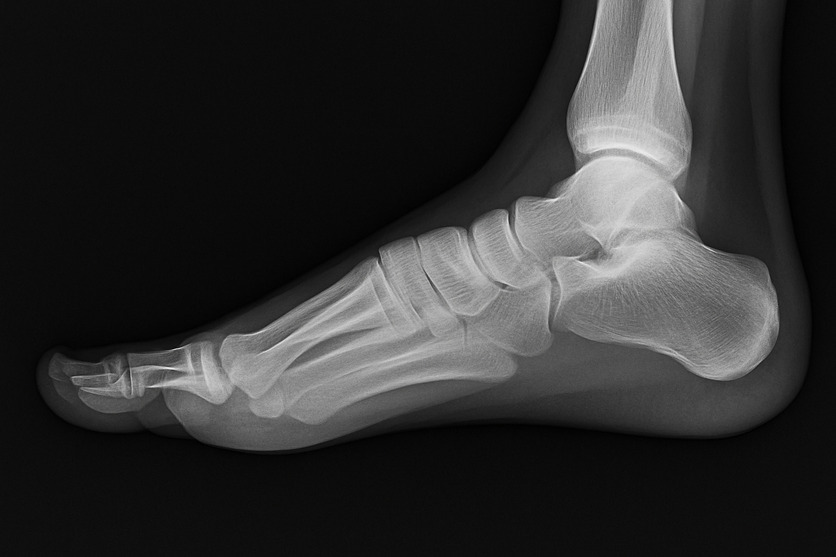

La radiografia del piede è un esame diagnostico che proietta su uno schermo immagini bidimensionali delle ossa di questa articolazione. Sostanzialmente, l'esame fornisce un'immagine in bianco e nero della parte interna del piede tramite l'applicazione di radiazioni ionizzanti (raggi X).

I tessuti possono apparire in diverse tonalità a seconda della quantità di radiazioni che assorbono. Più un tessuto è denso, maggiore è la quantità di radiazioni che assorbe e più chiaro il tessuto stesso apparirà nell'immagine radiografica. Le ossa, essendo molto dense, appaiono quasi bianche mentre muscoli, legamenti e tendini si manifestano in diverse tonalità di grigio.

Una radiografia del piede è in grado di mostrare le ossa tarsali (caviglia), metatarsali (ossa della parte anteriore del piede) e le dita (falangi).

Il tecnico radiologo può effettuare diverse proiezioni: solitamente, al fine di ottenere una visione completa delle strutture ossee, vengono acquisite tre immagini:

- Antero-posteriore (vista frontale);

- Laterale;

- Obliqua a 45 gradi.